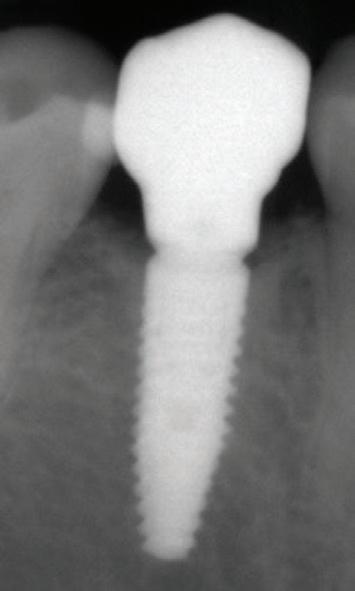

Figure 1: Radiographic Image of implants do not demonstrate bone loss due to the bisecting angle of the radiograph taken.

Figure 2: Radiographic image in a paralleling technique of implants dem onstrate moderate peri-implantitis with bone loss that will necessitate treatment.